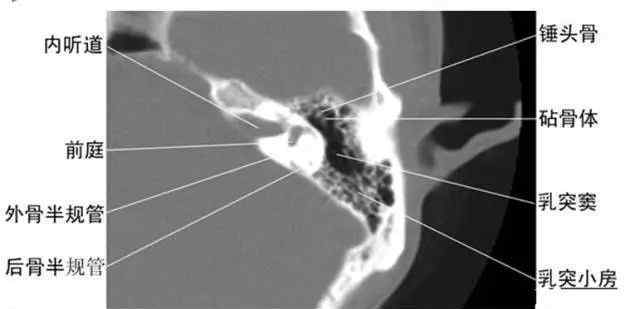

收集全身ct图谱。

中国医学网提供图像学习专题,帮助您快速学习如何阅读电影。综合讲解:胸像,脑像,腹像,骨科像…